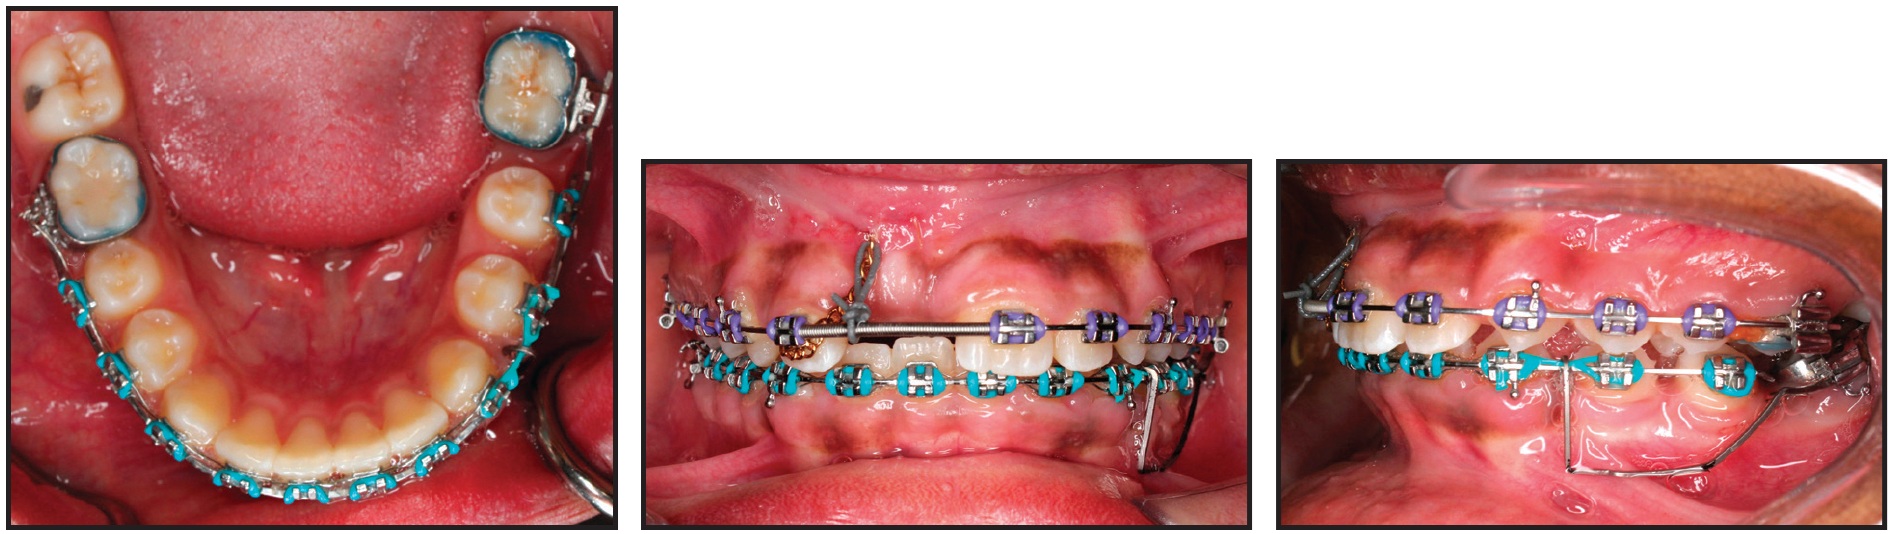

To further level and align the uprighted second molar with the rest of the lower arch, a continuous .016" x .022" nickel titanium archwire was placed. Three months later, an .019" x .025" stainless steel archwire was placed and a 1.8mm x 8mm mini-implant** was inserted interdentally between the lower left premolars. The lower left second-premolar bracket was removed, and bands were placed. A lower alginate impression was sent to the laboratory for fabrication of the previously described molar protraction appliance (Fig. 8).

Fig. 8 After 16 months of treatment, lower molar-protraction appliance cemented in place; stainless steel power arm splinted to mini-implant between lower left premolars and cinched in buccal premolar tube for indirect anchorage.

Every six weeks, the appliance was reactivated by attaching new elastomeric chain on both the buccal and lingual sides. The lower left second molar was mesialized in nine months, with only .5mm of anchorage loss of the second premolar (Fig. 9). The appliance was then removed, and a panoramic x-ray indicated that the movement was close to translation. At this point, the buccal segments were in an end-on Class II relationship. A fixed-functional appliance (Forsus Fatigue Resistant Device*) was then delivered to be worn for six months. After the anteroposterior discrepancy was corrected, finishing was carried out with .016" x .022" beta titanium archwires and light seating elastics.